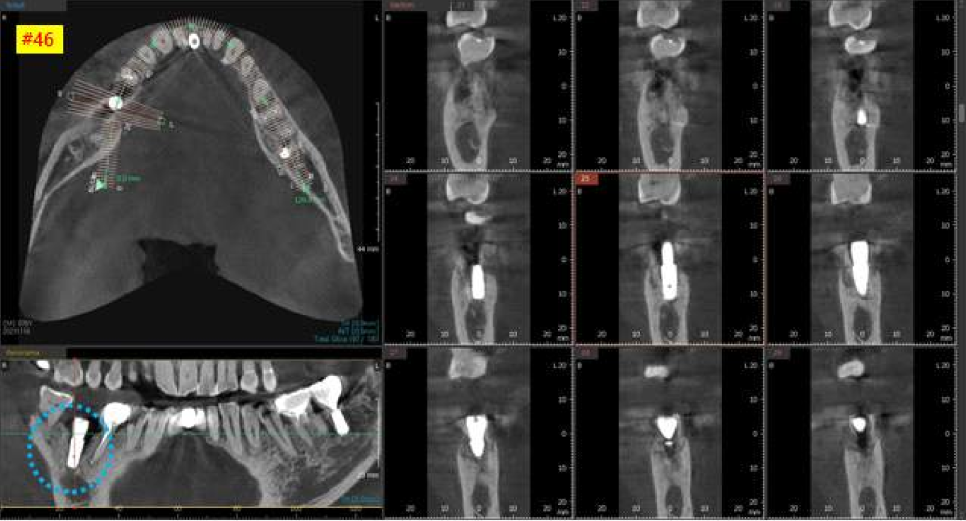

다음 날, 오른쪽 아래 큰어금니 수술을 진행하였습니다.

아래 어금니 같은 경우에는

신경이 손상되지 않도록 수술하는 것이 가장 중요합니다.

어금니 뿌리 아래부분에 ‘하치조신경’이라는 신경이 지나가는데

손상되면 안면마비가 올 수 있기 때문에 항상 조심해야 합니다.

3차원 CT사진에서 빨간색으로 표시해놓은 신경관을

피할 수 있도록 CT를 분석하고

이에 맞는 직경과 길이의 임플란트를 선택하여

수술을 시작하였습니다.

신경관을 피하고 생겼던 염증을 모두 제거하고

아주 잘 식립되었습니다. ^^

염증이 녹여놨었던 부족한 뼈는

뼈이식으로 더 단단하게 고정해주었습니다.

다행히 뼈이식을 한 덕분에

염증이 많았지만 수술 이후 초기 고정력이 잘 나왔습니다.